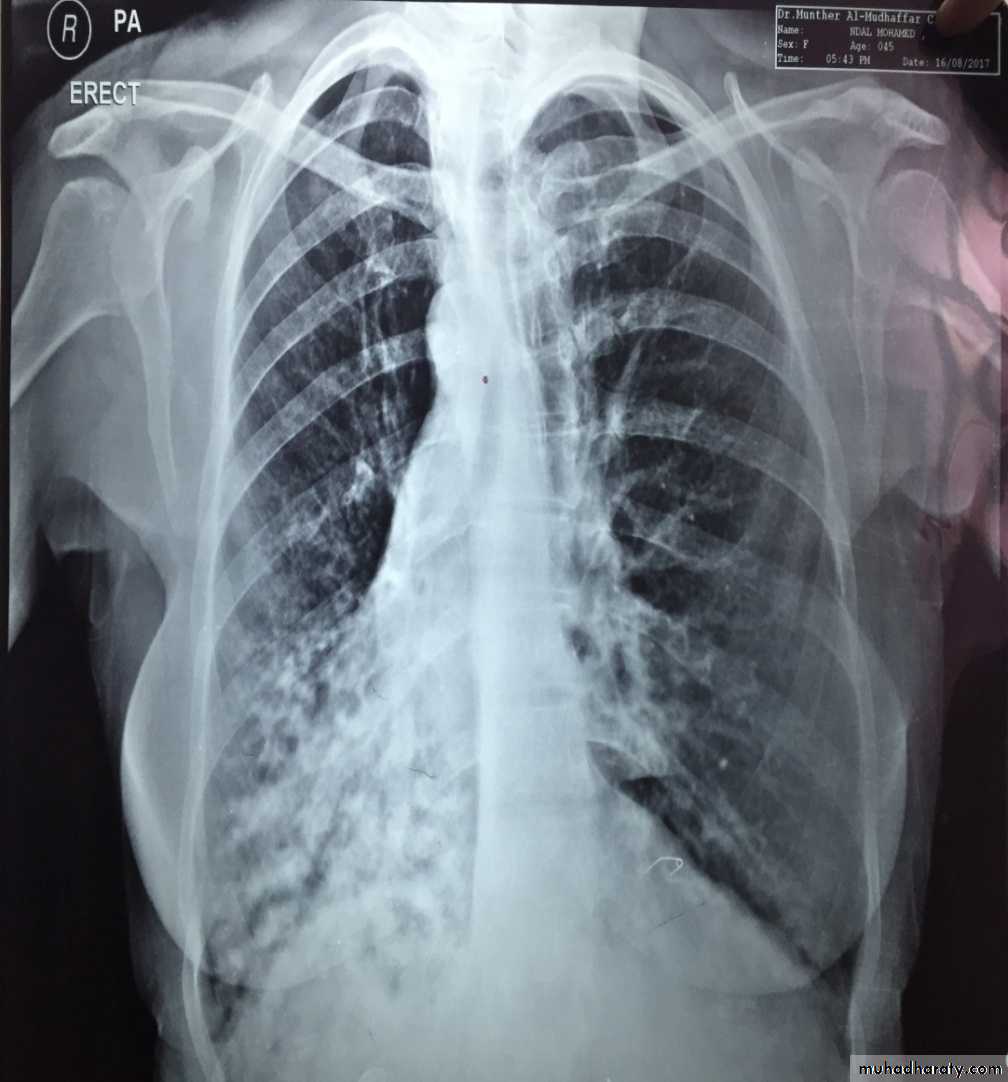

Bronchectasis

Abnormal irreversible dilatation of bronchioles with thickening of their walls . Presented with recurrent pneumonias & haemoptysis ..Types:Cystic

Fusiform

Cylendrical

In which the bronchiole is wider than the near by vascular branch

Causes –infancy & childhood infection

-TB

-pulmonary fibrosis

-cystic fibrosis

-immotile cilia syndromes